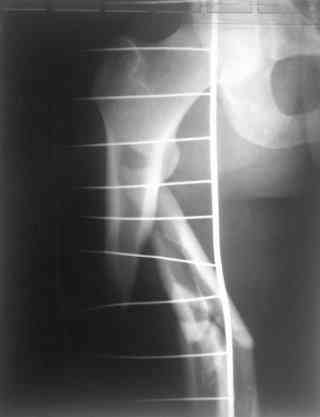

Надеюсь сейчас показать перелом, а потом синтез.

Вложение не в текстовом формате было извлечено…

Имя     : 1.jpg

Тип     : image/jpeg

Размер  : 7793 байтов

Описание: отсутствует

Url     : http://weborto.net:8080/pipermail/ortho/attachments/20070925/7aabe9cf/attachment-0005.jpg